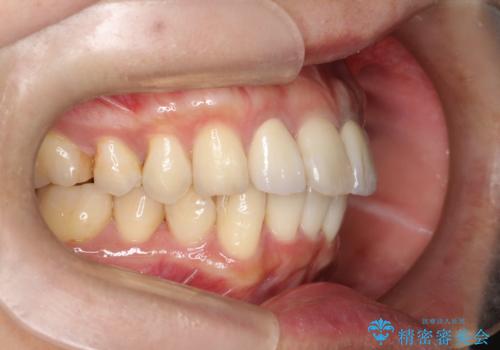

- 全体的なガタガタと前歯をきれいにしたいとのことで来院されました。

下の歯は重度のガタガタがあり、上の前歯は何本かが神経の治療がしてある状態でした。

インビザラインにて歯並びを整え、上顎の前歯にセラミックを装着する計画としました。

セラミックと矯正を組み合わせることにより、審美的にも機能的にも改善することができました。